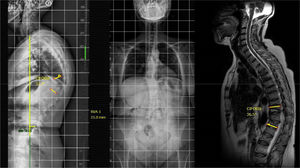

Dentro del grupo de la deformidad local (estadio 1), esta puede ser flexible (1A), si se observa una reducción de la angulación mayor del 50% en el decúbito con respecto a la radiografía (fig. 2) en bipedestación o rígida (1B), cuando no se ve una reducción con el decúbito (fig. 3)13. Por último, esta deformidad local, puede estar compensada (C) cuando la teleradiografía en bipedestación el SVA está en parámetros normales, o no compensada (NC), cuando la teleradiografía demuestra un SVA fuera de rango. Conviene recordar que el SVA está ajustado a la edad, y no buscamos una corrección tan exigente en el paciente anciano como en el paciente joven8.

Ilustración de un caso con estadio 1ANC, en el que sin necesidad de realizar una osteotomía tricolumnar se observa una muy buena reducción intraoperatoria y se realiza una instrumentación larga percutánea T4-L2 y vertebroplastia de L3, L4 y L5 por presentar fracturas a dicho nivel.1 ANC: deformidad secundaria a fractura vertebral osteoporótica Angular, Flexible y No Compensada.